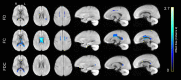

Aging is associated with widespread alterations in cerebral white matter (WM). Most prior studies of age differences in WM have used diffusion tensor imaging (DTI), but typical DTI metrics (e.g., fractional anisotropy; FA) can reflect multiple neurobiological features, making interpretation challenging. Here, we used fixel-based analysis (FBA) to investigate age-related WM differences observed using DTI in a sample of 45 older and 25 younger healthy adults. Age-related FA differences were widespread but were strongly associated with differences in multi-fiber complexity (CX), suggesting that they reflected differences in crossing fibers in addition to structural differences in individual fiber segments. FBA also revealed a frontolimbic locus of age-related effects and provided insights into distinct microstructural changes underlying them. Specifically, age differences in fiber density were prominent in fornix, bilateral anterior internal capsule, forceps minor, body of the corpus callosum, and corticospinal tract, while age differences in fiber cross section were largest in cingulum bundle and forceps minor. These results provide novel insights into specific structural differences underlying major WM differences associated with aging.